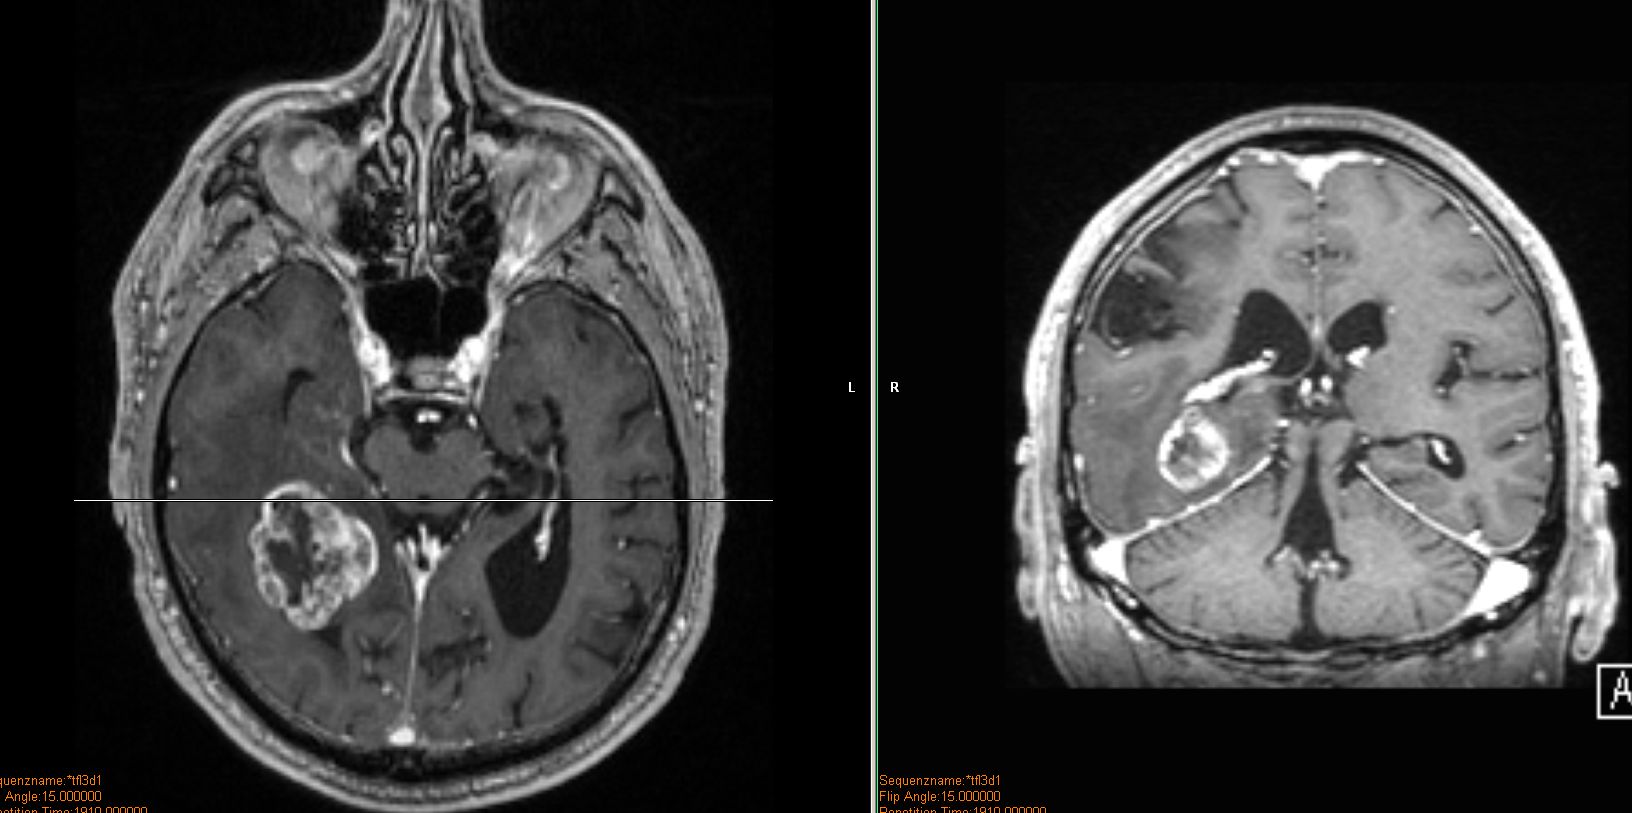

| MRT: multiple Hirnmetastasen | Adenokarzinom der Lunge. MRT-Untersuchung des Hirns. | |||

![]() |